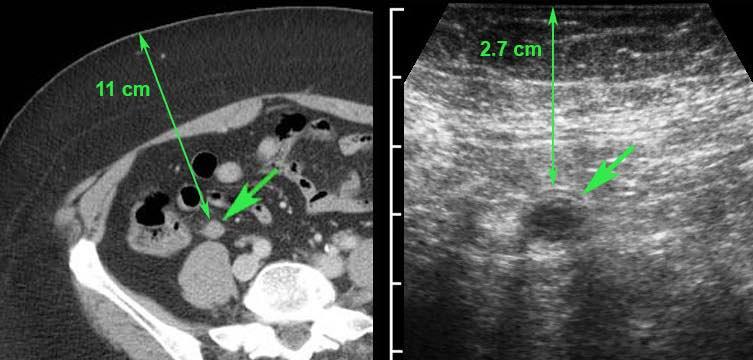

Ở người phụ nữ mang thai 11 tuần này, siêu âm xác nhận thai trong tử cung còn nguyên vẹn đồng thời phát hiện viêm ruột thừa cấp.

Lưu ý sự khác biệt về thang đo cm.

Phẫu thuật nội soi cắt bỏ ruột thừa viêm đã được thực hiện thành công.

Ở bệnh nhân béo phì này, CT xác định một ruột thừa nằm sâu, có thể đang viêm (mũi tên) ở khoảng cách 11 cm tính từ da.

Siêu âm tập trung với kỹ thuật ép dần (graded compression) đã rút ngắn khoảng cách này xuống còn < 3 cm, cho phép sử dụng đầu dò tần số cao, qua đó cho thấy ruột thừa không thể ép xẹp và đang trong tình trạng viêm (mũi tên).